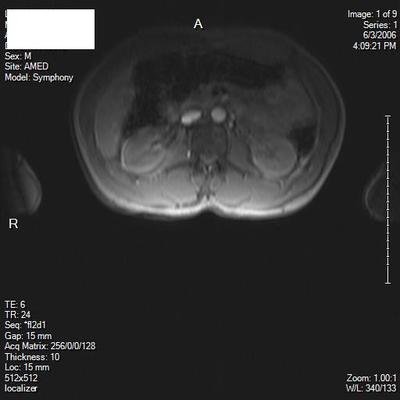

I'm 35 years old, male. Right hip pain, started as low back pain. Herniated disc L5S1, treated with ESI injections. Still have hip pain. Hurts when I flex my leg, SLR pain at about 45 degrees. My MRI and Xray are only of lumbar spine, however, do you see any abnormality of any bony or soft tissue of hip on these images? I understand it could be sciatica, which was the easiest thing they could come up with.

However, since the ESI injections did not provide much relief, I'm hoping you might see something on these that would point to an alternative theory of my hip pain, limitation of flexibility in hip.

Two of the scan views are poor and I'm unable to determine what level; there's a suggestion of the fat squeezed out of the IVF on the right, but I wouldn't much store from that.

From what's visible of the hips they appear normal to me.

When you say fat squeezed out IVF? What does this mean?

How could this cause pain and limitation of raising the leg?

I'm trying to locate any other pathology. Is their any muscle atrophy? Or other bursitis, soft tissue, tendon?

There's normally fat in the IVF; if it's been squeezed out there's likelihood of a disc prolapse into the foramen.